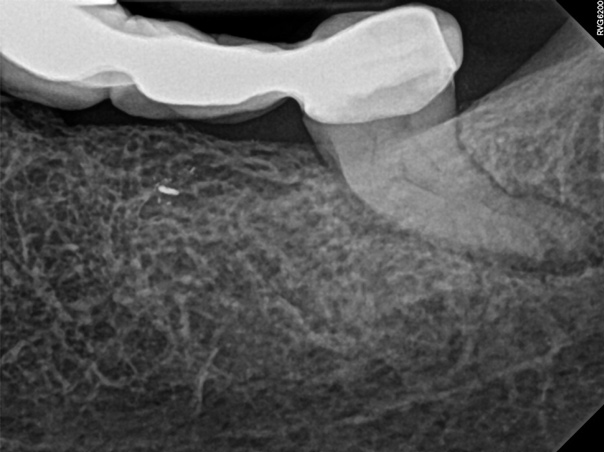

The second case study is that of a healthy 88-year-old woman who presented with significant bone loss on the mesial and apical aspect of tooth No. 18, which would suggest potentially a vertical fracture in the tooth (Figure 9 and Figure 10). The clinician had initially recommended extraction, which they informed the patient would likely be the best course of action, especially given that she had plenty of bone anterior to the tooth to place implants. When the recommendation of extraction was made to the referring dentist, he had some resistance because both he and the patient were interested in saving the tooth. Although the clinician initially stood firm on the recommendation, he received a call from the general dentist about a month later. He further expressed their desire to save the tooth, and he asked if the endodontist thought the new technology, the GentleWave Procedure, could be a solution. The informed consent was obtained and the patient was scheduled for treatment. Because the canal was quite calcified apically, a defined working length could not be determined. Obturation was performed using warm vertical condensation of gutta-percha.

Fig 9. Case 2: Significant bone loss on the mesial and apical aspect suggested a potential vertical fracture (Fig 9 and Fig 10). Radiographic images were taken immediately postoperatively (Fig 11) and 7 months postoperatively (Fig 12).

Figure 9

Fig 10. Case 2: Significant bone loss on the mesial and apical aspect suggested a potential vertical fracture (Fig 9 and Fig 10). Radiographic images were taken immediately postoperatively (Fig 11) and 7 months postoperatively (Fig 12).

Figure 10

Fig 11. Case 2: Significant bone loss on the mesial and apical aspect suggested a potential vertical fracture (Fig 9 and Fig 10). Radiographic images were taken immediately postoperatively (Fig 11) and 7 months postoperatively (Fig 12).

Figure 11